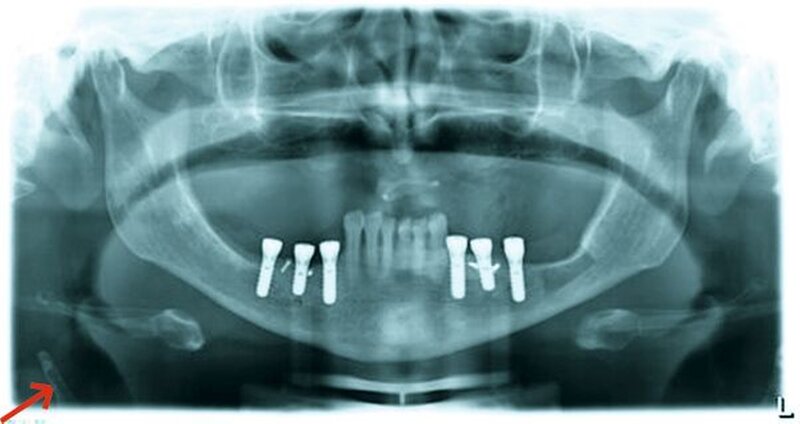

• Carotissklerose im OPTG beachten und eine neurologische Diagnostik veranlassen